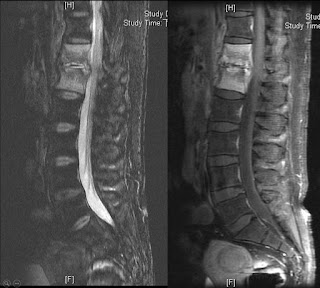

核磁共振上顯示第4/5腰椎及第5腰椎第一薦椎的椎間盤已有退化情形(顏色相對於其他節較黑),另外合併第四五腰椎的椎管狹窄(spinal stenosis)及輕微的椎間盤突出 (disc buldging)。

| 第四五腰椎椎管狹窄神經壓迫, 腰椎最下面兩節輕微退化 |